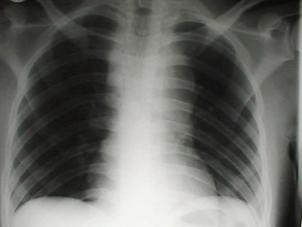

Pneumotorace sufocant bilateral Pneumotorace sufocant stang

Pneumotorace

sufocant stang Pneumotorace

sufocant drept Pneumotorace

sufocant drept